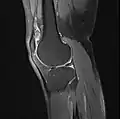

MRI

Both anterior cruciate ligament (ACL) and posterior cruciate ligaments (PCL) are hypointense on both T1 and T2 weighted images of MRI. However, some high signal striations are often seen at the distal part of the ACL, making ACL higher intensity than PCL on MRI scans.[17]

Knee MRI (T1 TSE sagittal)- Knee MRI (sagittal TSE FS)